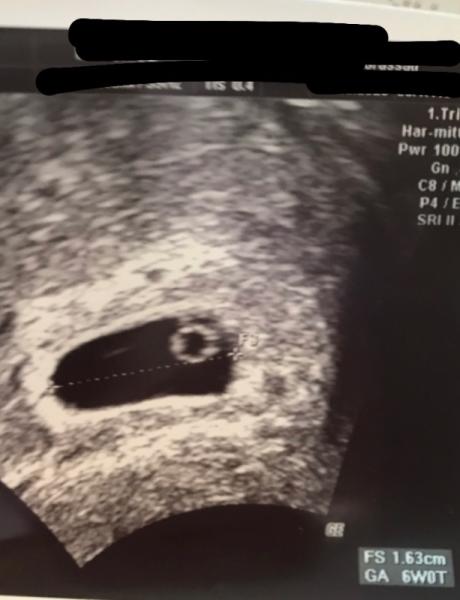

Hallo, tolles Foto hatte gestern eine schnelle Kontrolle leider ohne ausmessen aber alles in Ordnung bin ca. ende der 6ssw., nächsten woche Dienstag hab ich wieder Kontrolle und da wird dann gescheit vermessen da sollte dann auch schon Krümmel mit herzschlag zu sehen sein liebe grüße

Bild zu